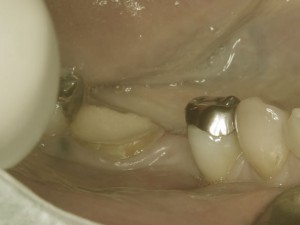

歯が痛いと来院された患者様です。

写真のように、歯が部分的にかけてしまっています。

さらに折れてしまった部分が歯の根にまで及んでしまっている状態で、神経も露出していました

痛みの原因は神経の露出だったので神経を抜く治療を早急に行いました。